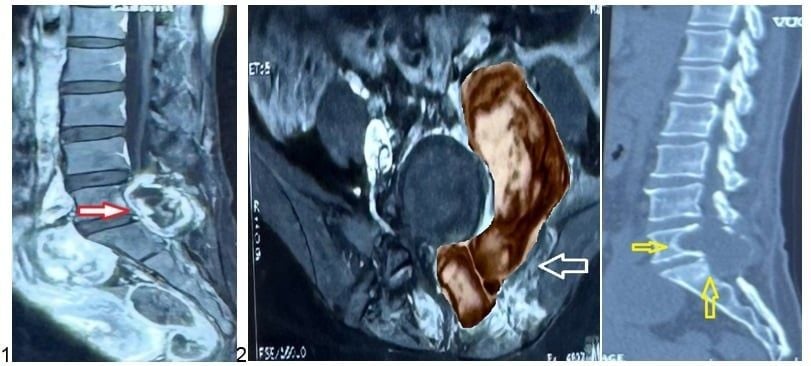

Hình 1, 2, 3: Ảnh chụp MRI và CT Scan trước phẫu thuật của bệnh nhân L. cho thấy khối u kích thước lớn (hình 2, mũi tên đỏ) xâm lấn các cấu trúc lân cận (hình 2, mũi tên trắng) và gây hủy xương vùng cột sống cùng (hình 3, mũi tên vàng).

Trước đó, chị L. từng được phẫu thuật lấy khối u vùng cột sống thắt lưng cùng (L5-S1) tại một bệnh viện chuyên khoa Ngoại thần kinh và được chẩn đoán là u sợi thần kinh lành tính (Schwannoma). Tuy nhiên, khi đến Bệnh viện Nhân dân 115, chị nhập viện trong tình trạng đau lưng nhiều, tê và yếu chân trái. Mỗi lần vận động mạnh, cơn đau và tê tăng lên khiến sinh hoạt hằng ngày bị ảnh hưởng nghiêm trọng. Kết quả chụp MRI cột sống thắt lưng cho thấy một khối u lớn dạng “hình quả tạ” ở vùng L5-S1, xâm lấn nhiều vị trí gồm cơ cạnh sống, cơ psoas, thân sống, cánh chậu và cả vùng phúc mạc. BS.CKII Lê Điền Sơn, Phó trưởng khoa Ngoại Thần kinh – Bệnh viện Nhân dân 115, chia sẻ: